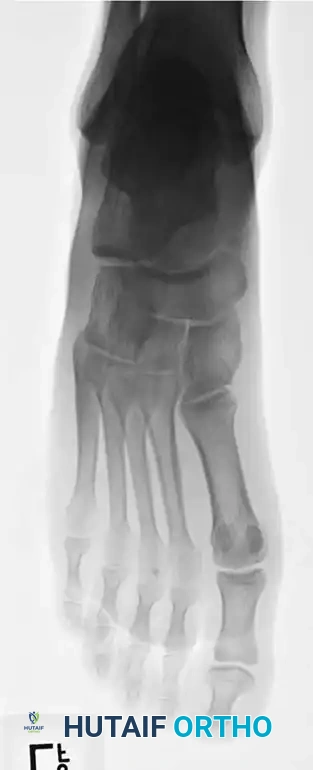

METATARSALS Surgical Diagram

Fig. 86-45 A-C. Type IA (DeLee) fifth metatarsal fracture in a collegiate soccer player, representing an ideal candidate for early intramedullary fixation.

Fig. 86-45 D-F. Postoperative imaging after robust fixation utilizing a variable pitch compression screw, ensuring excellent compression across the fracture site.